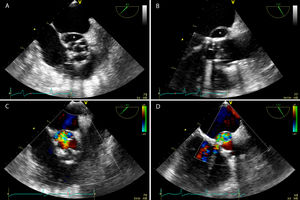

A transesophageal echocardiography (Fig. 1A and B) was performed and demonstrated a biological prosthesis in aortic position with reduced opening and a perivalvular echo-free saccular cavity along with the non-coronary and left coronary cusps, corresponding to a pseudoaneurysm. With Color-Flow Doppler (Fig. 1C and D) it was possible to observe a communication between the perivalvular cavity and the cardiovascular lumen with a high-velocity jet entering the left ventricle outflow tract.